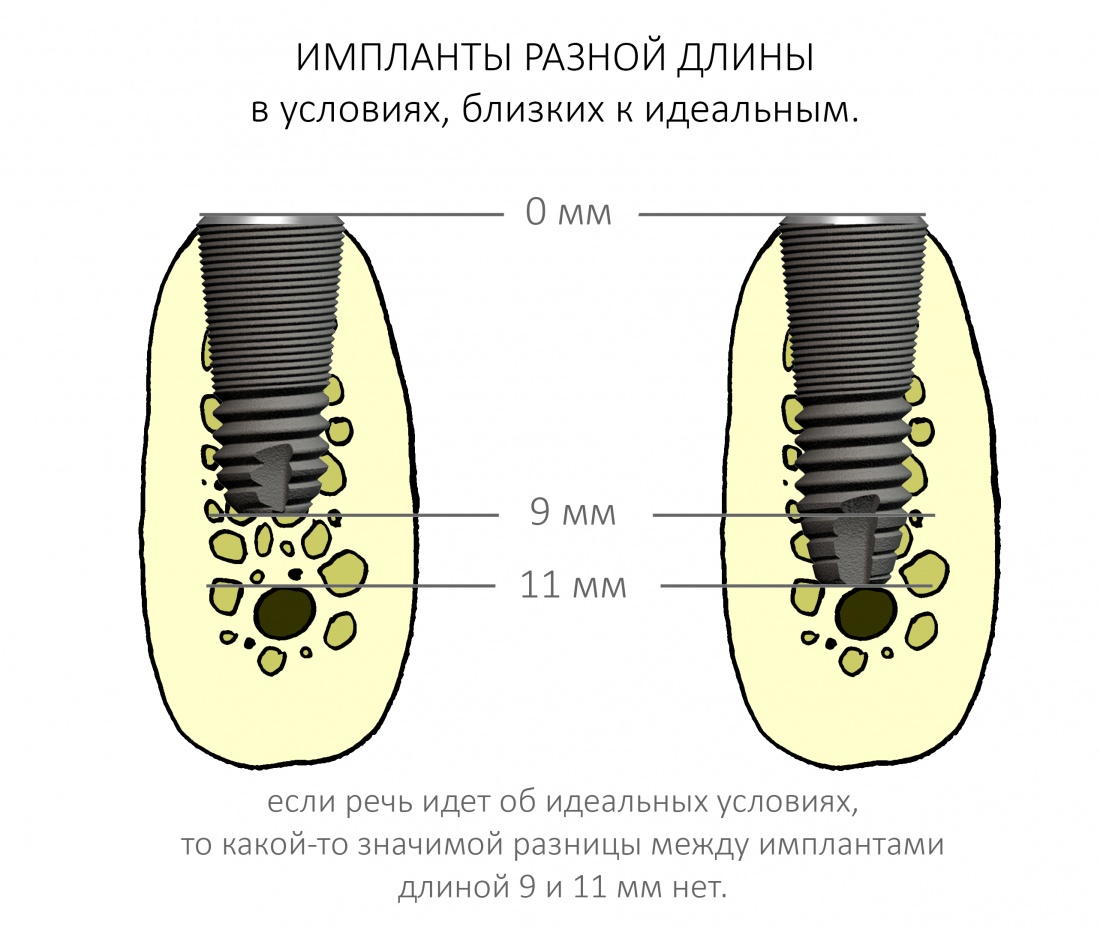

В этом случае длина имплантата большого значения не имеет, и разницы в интра- и послеоперационном поведении импланта длиной 9 и 11 мм не будет. То есть, в идеальных (либо близких к идеальным) условиях для имплантации, длина имплантата не имеет решающего значения:

НО! Планируя операцию в области седьмых зубов, либо при затрудненном открывании рта, учитывайте возможность завести инструменты в область имплантации. В таких случаях, возможно, имеет смысл склоняться к использованию имплантатов длиной не более 10 мм, ибо с большей длиной просто будет сложнее работать:

- Длина имплантата имеет значение только с точки зрения достижения первичной стабильности при немедленной имплантации. В условиях, близких к идеальным, длина не столь важна.